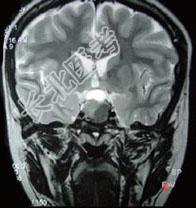

单项选择题男,47岁, 视物模糊数月,头痛、恶心、呕吐3天, 行MRI检查如图,最可能的诊断为 ( )

A、颅咽管瘤

B、脑膜瘤

C、垂体瘤并出血

D、蛛网膜囊肿

E、表皮样囊肿